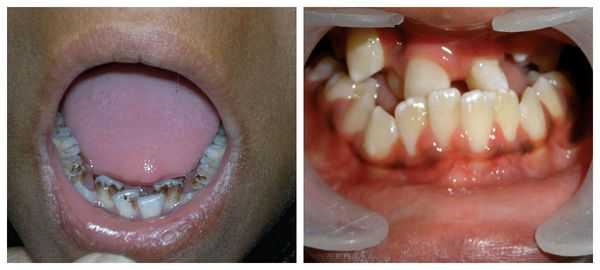

В разговорной речи расщелину неба часто называют «волчьей пастью», а расщелину губы – «заячьей губой». Однако в профессиональном мире это не принято – подтверждает заведующий 1 хирургическим отделением ДГКБ святого Владимира, доктор медицинских наук, профессор Дмитрий Юрьевич Комелягин.

– Мы никогда так не называем своих пациентов и их заболевания. Людям это очень обидно слышать. Эти особенности называются «врожденная односторонняя расщелина верхней губы, альвеолярного отростка и неба» и «врожденная двусторонняя расщелина верхней губы, альвеолярного отростка и неба».

Важный момент в лечении расщелины альвеолярного отростка – ортодонтическая подготовка. То есть, сначала ортодонт добивается правильного положения фрагментов верхней челюсти относительно друг друга и относительно нижней челюсти, а потом уже к коррекции приступают хирурги.

В случае успешной операции пациенты приходят потом для контрольного наблюдения раз в полгода. Хирург и ортодонт следят за тем, как формируются рубцы, верхняя челюсть, нет ли деформации носа. Иногда приходится снова делать хирургическую коррекцию. Но эти решения важно принимать совместно с ортодонтом. Если рост верхней челюсти не закончен, хирургическое вмешательство может навредить.